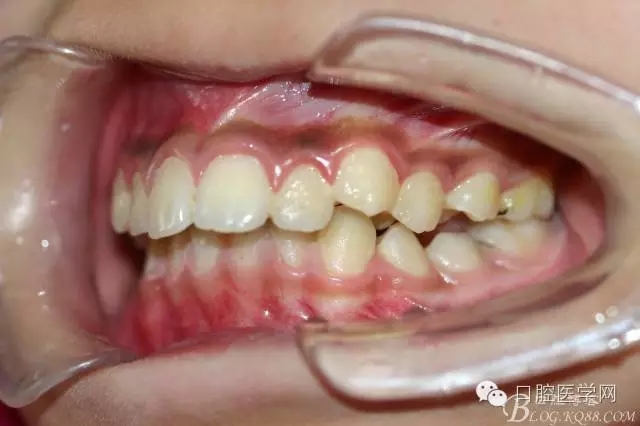

正畸查:替牙合。第一恒磨牙中性合。上牙弓尖圓型下牙弓方圓型。前牙覆合3度覆蓋7.5mm。下前牙咬到上舌側(cè)牙齦。上頜擁擠4.0mm,下頜擁擠

3.0mm。上頜稍前突下頜后縮,上下唇前突,上前牙覆蓋下唇,下唇外翻。面下三分之一過(guò)短,頦唇溝明顯,開(kāi)唇露齒,頦饜窩明顯。顳下頜關(guān)節(jié)開(kāi)閉口無(wú)彈響,無(wú)壓痛,開(kāi)口型開(kāi)口度正常。

正畸前照片: